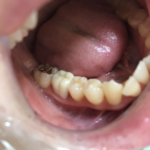

セラミックって綺麗

2022年1月27日(木)

今ある銀歯を全て白い歯にしたいと

ご来院していただいている患者様です。とても綺麗な女の方です。マスク生活のうちに美活動にはげまれるそうです。💕

その方に似合う色合わせをし型をとりセラミックセットとなります。ツルツルしていて舌触りも最高です。あと一歩奥を銀歯をセラミックにしたらこの方の処置は終了となります。口元も素敵になりさらにきれいになられますね。